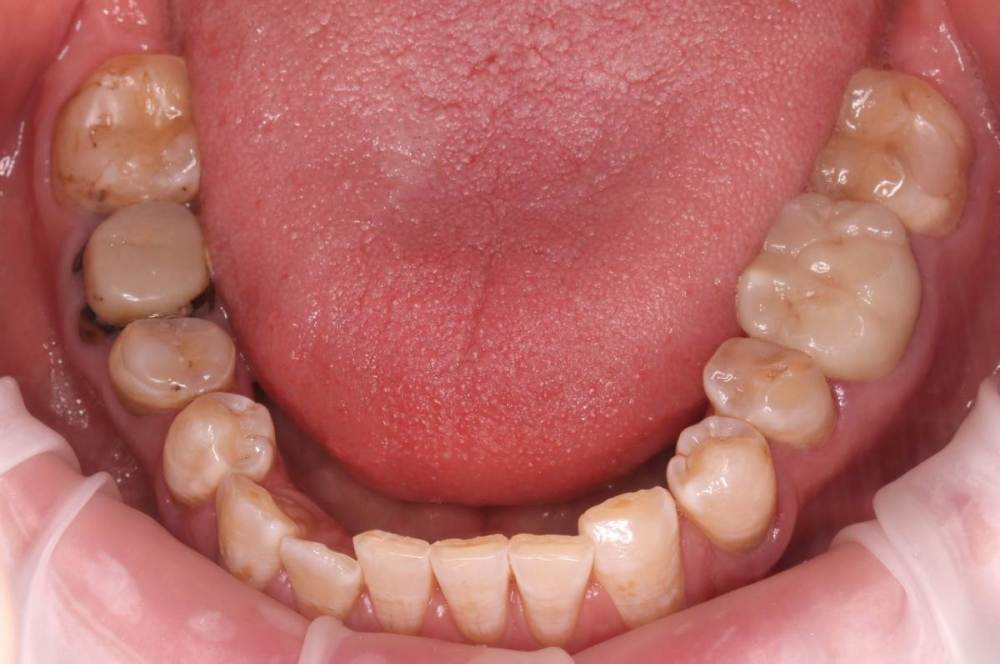

Роман1982 Опубликовано 25 мая, 2021 Поделиться Опубликовано 25 мая, 2021 Добрый день! Очень хотелось бы услышать объективное мнение специалистов. 40 лет На верхней челюсти от рождения не хватает двух резцов (12 и22) Перекрестный прикус В принципе, особо не беспокоит, хотя есть щелчки в суставе слева, если широко открывать челюсть. Из-за неправильно проводимого ранее лечения, встал вопрос об удалении в ближайшее время 25 и 26 зуба сверху и 46 снизу (на фото обведены красным). Ортопед рекомендовал пройти ортодонтическое лечение, т.к. в противном случае в дальнейшем могут возникнуть сложности с имплантами и коронками, может ухудшиться ситуация с суставом. Вот пытаюсь взвесить все за и против. Понимаю, что прикус было бы желательно исправить. Но! При текущем состоянии зубов не навредит ли это им еще больше? Исправление прикуса повлечет за собой необходимость установки на верхней челюсти еще двух дополнительных имплантов (на месте отсутствующих12 и 22). После исправления прикуса велика вероятность тотального протезирования. По словам того же ортопеда, может не хватить высоты сустава и тогда на все зубы понадобиться устанавливать коронки. Стоит ли затевать ортодонтическое лечение в данной ситуации или лучше не трогать то, что как-то функционировало 40 лет? Хотелось бы услышать аргументирование мнение. Ссылка на комментарий

Brigita Опубликовано 1 июня, 2021 Поделиться Опубликовано 1 июня, 2021 я считаю, что ортодонтия Вам показана. Те пятна, которые Вы видите - это определенная форма флюороза, эмаль, конечно страдает. Но, при правильно спланированном лечении и хорошей гигиене, брекеты не ухудшат состояние эмали, но улучшит состояние Вашего организма в целом 1 Ссылка на комментарий